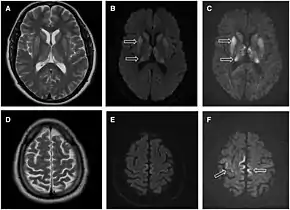

Imaging of the brain may be performed during medical evaluation, both to rule out other causes and to obtain supportive evidence for diagnosis. Imaging findings are variable in their appearance, and also variable in sensitivity and specificity.[43] While imaging plays a lesser role in diagnosis of CJD,[44] characteristic findings on brain MRI in some cases may precede onset of clinical manifestations.[45]

Brain MRI is the most useful imaging modality for changes related to CJD. Of the MRI sequences, diffuse-weighted imaging sequences are most sensitive.[46] Characteristic findings are as follows:

- Focal or diffuse diffusion-restriction involving the cerebral cortex and/or basal ganglia. In about 24% of cases DWI shows only cortical hyperintensity; in 68%, cortical and subcortical abnormalities; and in 5%, only subcortical anomalies.[47] The most iconic and striking cortical abnormality has been called "cortical ribboning" or "cortical ribbon sign" due to hyperintensities resembling ribbons appearing in the cortex on MRI.[48] The involvement of the thalamus can be found in sCJD, is even stronger and constant in vCJD.[49]

- Varying degree of symmetric T2 hyperintense signal changes in the basal ganglia (i.e., caudate and putamen), and to a lesser extent globus pallidus and occipital cortex.[44]

- Cerebellar atrophy